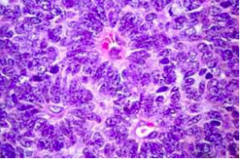

malignant cells showing pleiomorphic, anisocytosic, and discohesive feature

Back